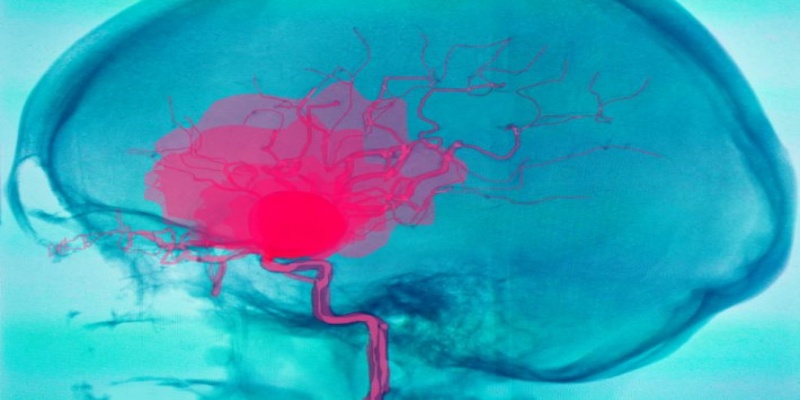

5) النزيف الدماغي

النزيف الدماغي

ترتفع مخاطر الإصابة بالنزيف الدماغي في فترة ما بعد الولادة المبكرة عند الأطفال الخدج بنسبة كبيرة جدا، فمن الهام معرفة أن هذه الحالة إذا كانت في صورتها الخفيفة، فيمكن للطفل أن يتعافى من تلقاء نفسه، ولكن إذا كانت هذه الحالة شديدة ومتفاقمة، فمن الممكن أن تتسبب في ترك عقابيل صحية لاحقا.

لذلك، يحتاج الأطفال الخدج عادة إلى فحص الموجات فوق الصوتية للدماغ فور الولادة حيث تساعد هذه الموجات أيضا في اكتشاف البقعة الكيميائية البيضاء حول البطينين، والتي يمكن أن تتسبب في حدوث خلل الحركة أو الشلل الدماغي.